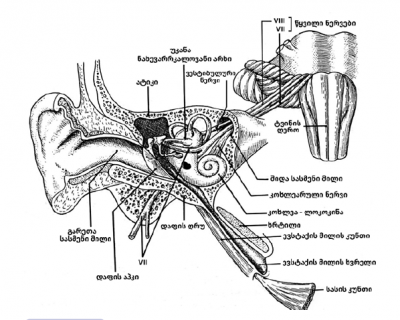

ეს ორგანო რამდენიმე ნაწილისაგან შედგება:

- გარეთა ყური – წარმოდგენილია ყურის ნიჟარით და გარეთა სასმენი მილით. მათ ფუნქციაში შედის ხმის შეგროვება. ყურის ეს ნაწილები ამოფენილია კანით, რომელიც, მეტწილად, დაფარულია თმით (რაც, შესაძლებელია, ფურუნკულის გაჩენის მიზეზი გახდეს) და გოგირდის წარმომქმნელი ჯირკვლებით. როგორც წესი, ეს ჯირკვლები გარეთა სასმენი მილის ირგვლივ არის განლაგებული. ყურის ნიჟარის კანი და ხრტილი ისე მჭიდროდ არის დაკავშირებული ერთმანეთთან, რომ კანის მცირედი ანთებაც კი იწვევს საშინელ ტკივილს.

- შუა ყური – წარმოდგენილია რამდენიმე ჰაეროვანი ღრუთი. ეს ღრუები ერთმანეთთან არის დაკავშირებული. ბოლოს ისინი ცხვირ-ხახას უკავშირდებიან ევსტაქის მილის მეშვეობით. უფრო კონკრეტულად კი ის წარმოდგენილია დაფის ღრუთი, რომელშიც სასმენი ძვლები მდებარეობს და მასტოიდური უჯრედებით. დაფის ღრუ ძალიან თხელი, ძვლოვანი ჯებირებით არის დაყოფილი. ევსტაქის მილი შუა ყურის ერთ-ერთი უმნიშვნელოვანესი ნაწილია, რომელიც პასუხისმგებელია შუა ყურის წნევის რეგულაციაზე და აკავშირებს მას ცხვირ-ხახასთან. ევსტაქის მილი დაფარულია რესპირატორული ლორწოვანი გარსით და მისი კუნთები ხახის კუნთებთან უნისონში მუშაობს. ისინი ყლაპვისას ხსნიან მილს, რაც უზრუნველყოფს შუა ყურის წნევის რეგულაციას.

- შიდა ყური ანუ ლაბირინთი შედგება ორი ნაწილისაგან – ლოკოკინა, ანუ კოხლეა, რომელსაც გააჩნია სმენის ფუნქცია და უტრიკულუსი და საკულუსი, თავიანთი ნახევარრკალოვანი არხებით, რომელიც წარმოადგენს წონასწორობაზე პასუხისმგებელ ორგანოს.

ამ ნაწილებში, ასევე, აღსანიშნავია ძირითადი ანატომიური ელემენტები:

- სმენის ნერვი, უფრო სწორად, სტატო-აკუსტიკური ნერვი, რომელიც აერთიანებს ვესტიბულარულ და კოხლეარულ ნერვულ ბოჭკოებს, ცენტრალური ვესტიბულარული გზებით მიემართება ცერებრალური ღეროსკენ და შესაბამისი კორტიკალური ბირთვებისკენ.

- დაფის აპკი და სასმენი ძვლების ჯაჭვი, რომელიც განთავსებულია დაფის ღრუში ანუ შუა ყურში, ასრულებს შემდეგ ფუნქციას: ის ახდენს ხმის კონცენტრირებას და გადასცემს მას შიდა ყურს. რომ არა ეს აპკოვან-ძვლოვანი სისტემა, აეროვანი რხევის გადაცემა შიდა ყურის სითხოვან სისტემაში იმდენად არაეფექტური იქნებოდა, რომ სისტემაში წარმოქმნიდა მხოლოდ 50-55 დეციბელს, ანუ, გამოიწვევდა ჩვენი სმენის 50%-ით დაქვეითებას.